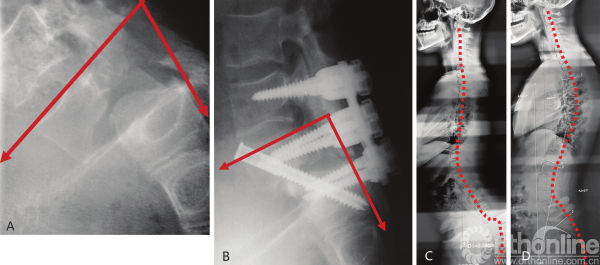

向上力线的其他表现包括矫正腰椎后凸的患者接受大型截骨术矫正后,颈椎前凸角度增加(图3-37,图3-38)。

图3-37 腰椎截骨术后的“向上力线”

A.术前腰椎X线;B.术后腰椎X线;C.术前颈椎X线;D.术后颈椎X线。C2~C7角减小较多,C1~C2角减小较小

图3-38 发育不良性脊柱滑脱术后的脊柱力线

A.术前腰骶椎X线;B.术后腰骶椎X线;C.全脊柱术前X线;D.全脊柱术后X线

手术治疗scheuermann病重建胸椎后凸导致颈椎前凸角度减小,腰骶后凸并伴有发育不良性脊柱滑脱者会出现腰前凸角度减小和胸椎后凸的增加(图3-39,图3-40)。